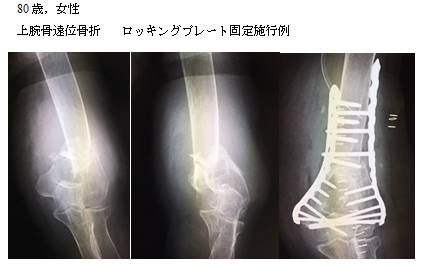

上腕骨遠位部骨折は、肘関節周囲の骨折のなかでも最も治療に難渋する骨折の一つとされています。こうした骨折に対する第一選択はロッキンプレートを用いた骨接合術ですが、高度粉砕例や偽関節例の場合には、プレート固定が困難な症例もあります。 AHGでは、必要な患者様に対して人工肘関節を施行しています。手技の確立と、人工関節の進歩により、安定した手術成績が得られています。